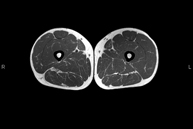

RM de Cuixa

RM de CuixaExploració ideal per estudiar les lesions en músculs isquiotibials i quàdriceps, sovint lesionats en esportistes. També permet una bona valoració de tendons i de nervis perifèrics. La durada aproximada és de 20 minuts. No utilitza radiació ionitzan.